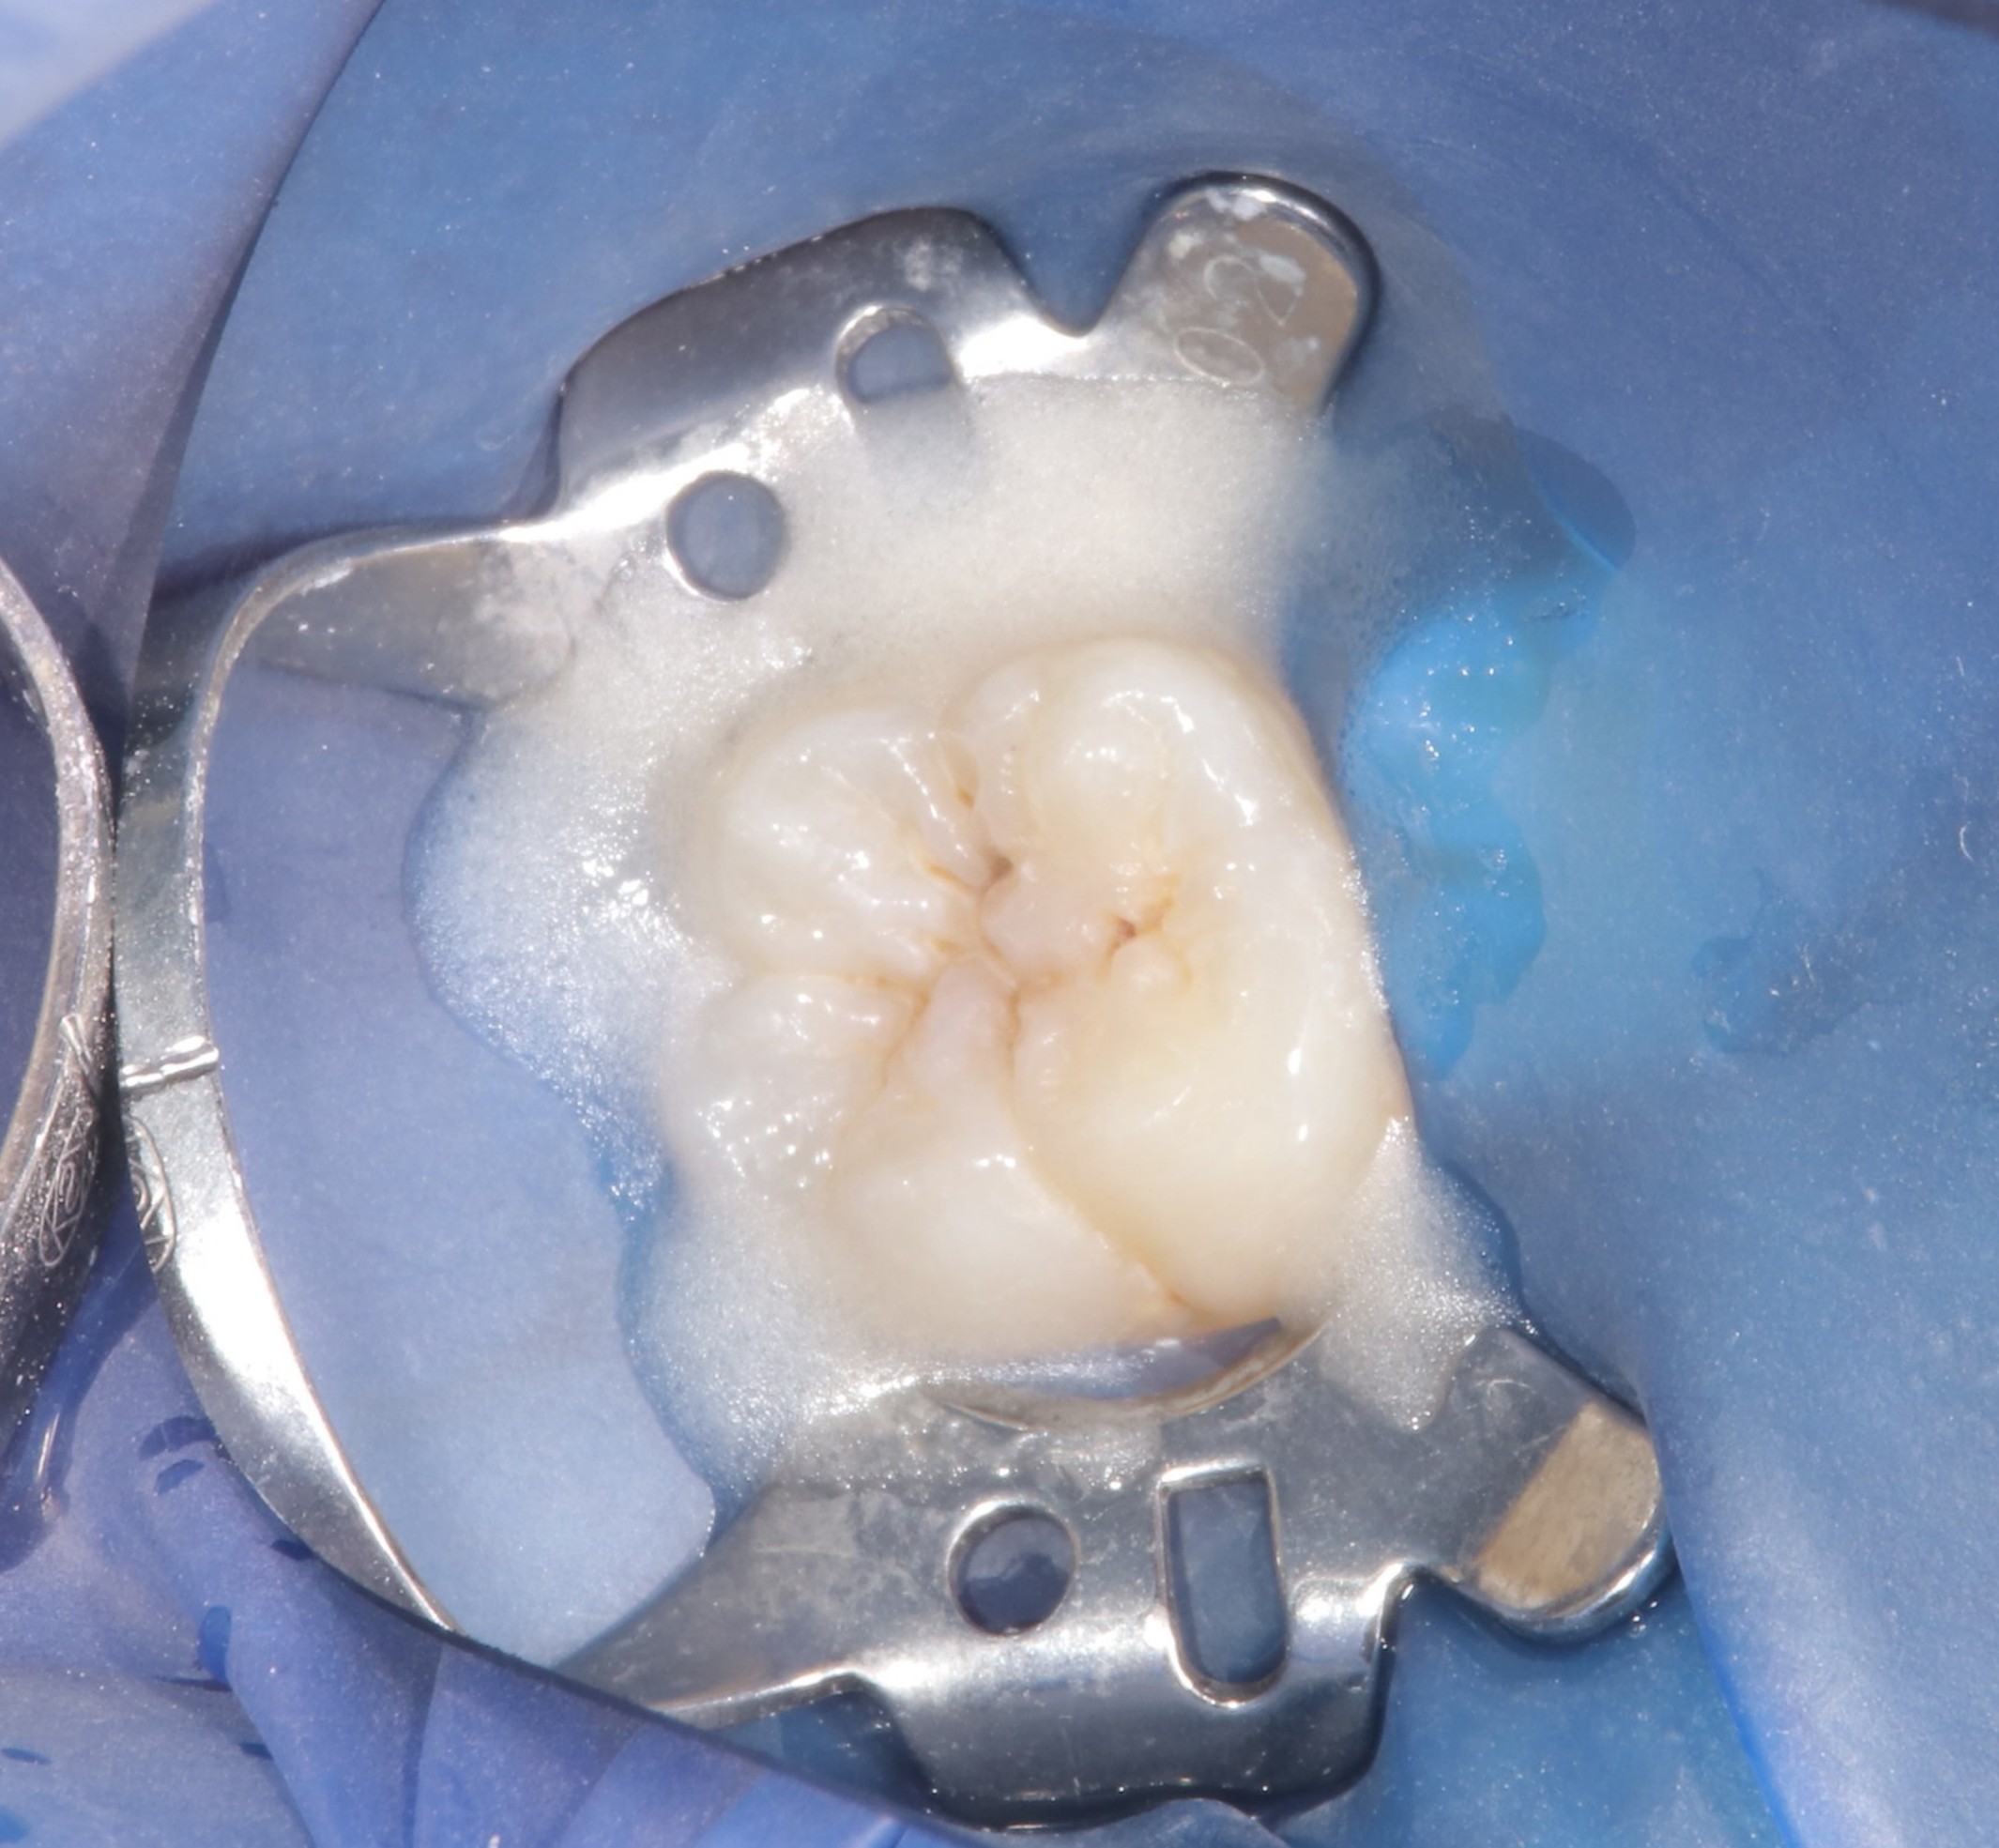

治療内容 虫歯を慎重に除去した後、

神経を保護する材料を用いて歯髄を保存し、修復処置を行いました。

その後、定期的に経過観察を行っています。